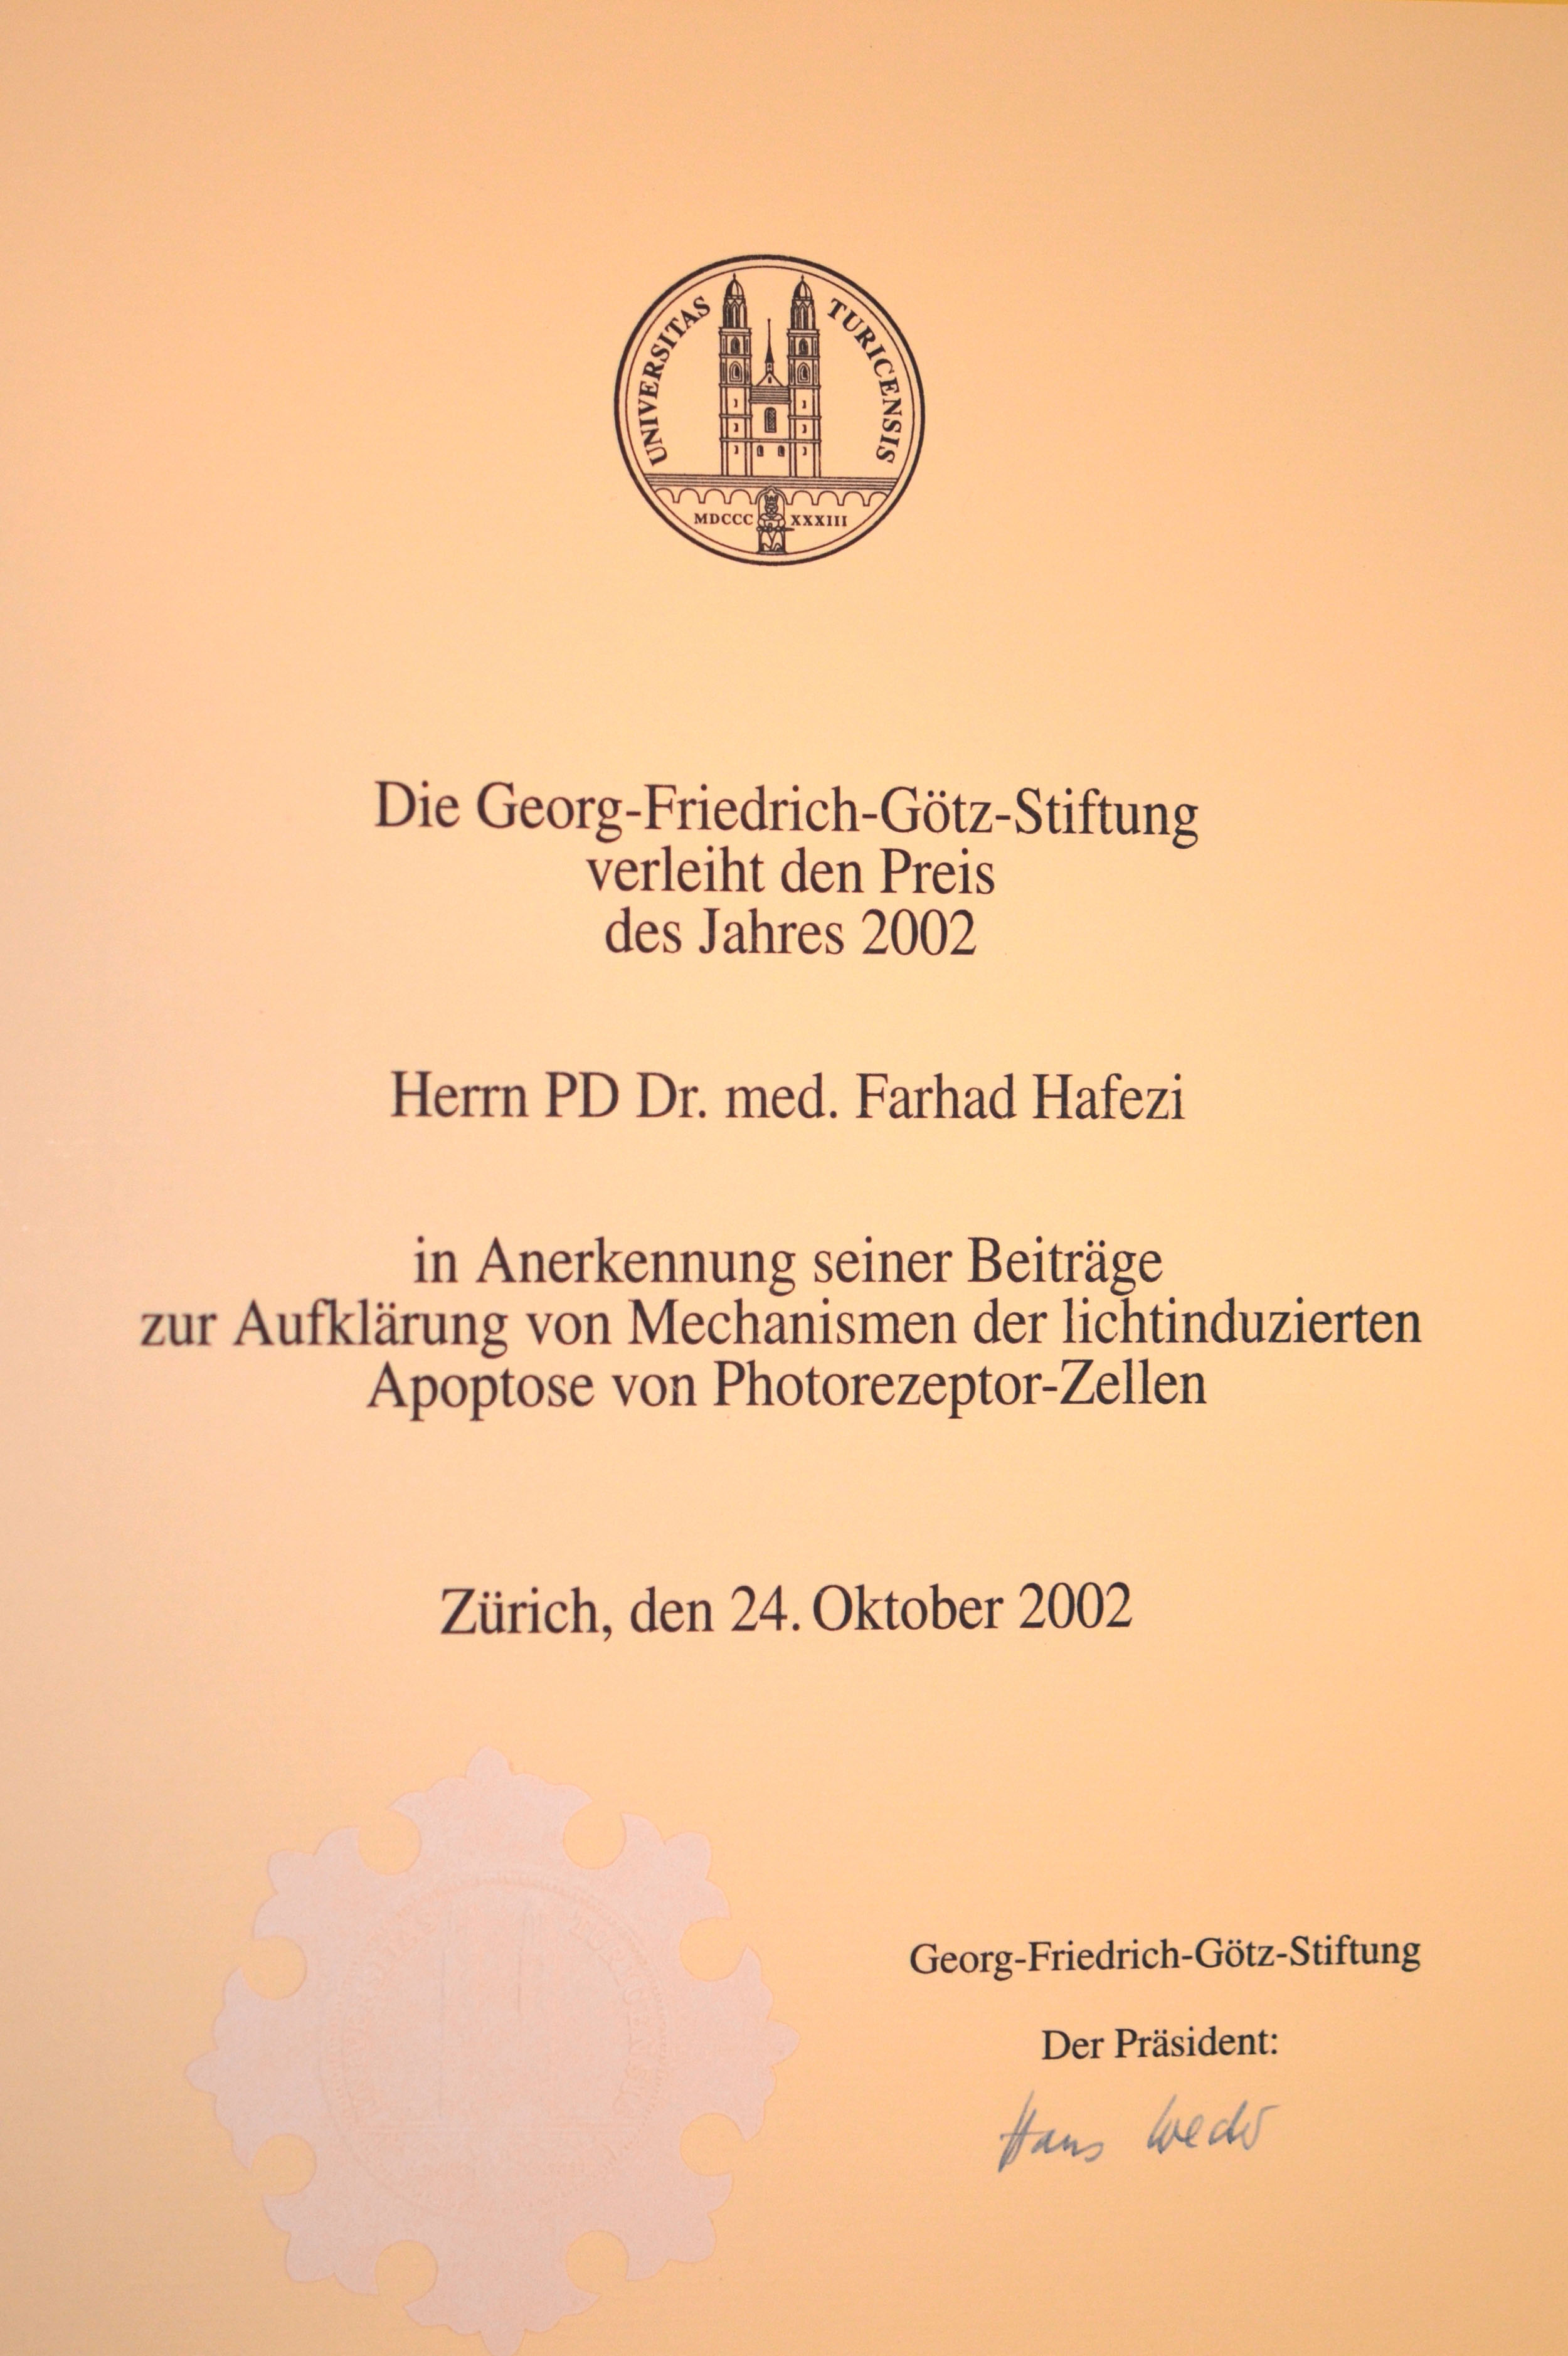

Highest medical distinction of the University of Zurich.